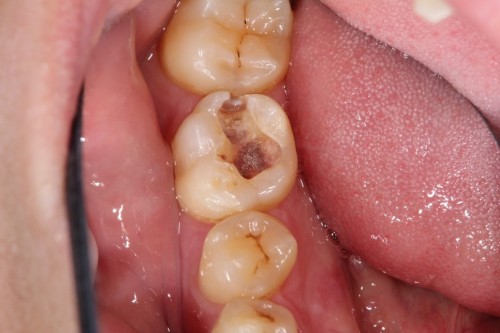

奥歯がしみるとの事でした。一見分かりませんが拡大鏡で確認して行くと虫歯が見つかりました。

虫歯を取った状態です。虫歯のみを取っています。

ここにマトリックスという金属製の薄い器具を入れて行き歯の形をなるべく再現できる様にします。

治療後の状態です。通常の型とりをする治療だと今回の数倍歯を削る事になります。歯は削れば削る程、脆くなりますので治療する事で歯の寿命を縮める事にもなり兼ねません。今回、最小限度のダメージで回復できました。歯も長持ちする事でしょう。

ダイレクトボンディング

費用6万円

リスクとして欠ける可能性がある(修復可能)。